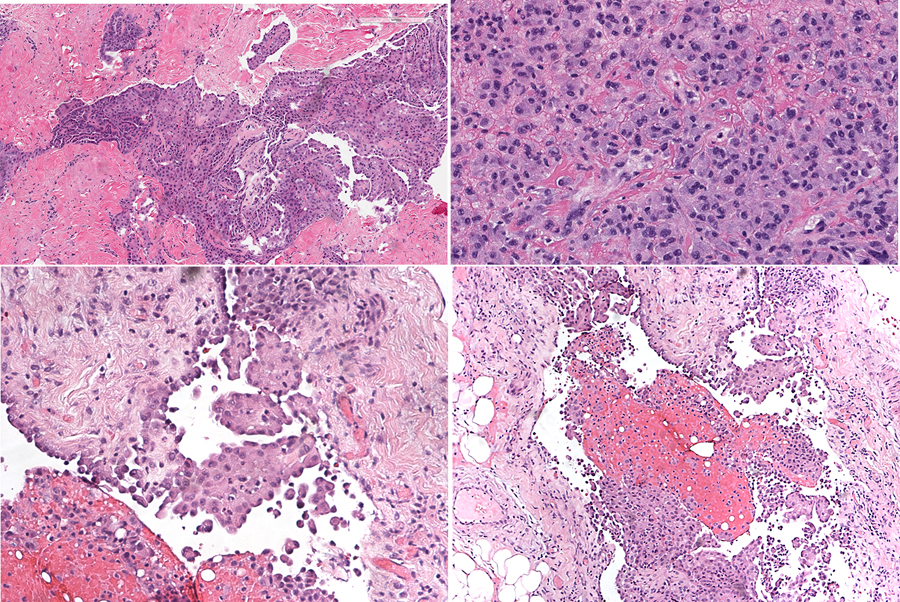

Nivolumab-induced peritonitis with peritoneal mesothelial hyperplasia mimicking metastatic mesothelioma

A 57-year-old man developed a mesothelial proliferation in the peritoneum, several months after he was diagnosed with biopsy-proven epithelioid mesothelioma of the pleura and having undergone several treatments with checkpoint inhibitor immunotherapy. The differential diagnosis was metastatic mesothelioma from the lung primary, versus a reactive process. A diagnosis of atypical mesothelial proliferation was made. Follow-up CT showed no evidence of abdominal disease 5 months later. The complication of serositis following checkpoint inhibitor therapy is reviewed, as well as the differential diagnosis between reactive mesothelial hyperplasia and epithelioid mesothelioma.